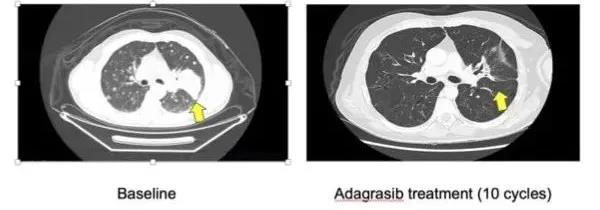

▽ Adagrasib治療前后的CT影像對比

早期臨床前試驗(yàn)結(jié)果表明,Adagrasib可以縮小腫瘤,而且患者的耐受性良好。研討會(huì)上報(bào)告的數(shù)據(jù)是來自一項(xiàng)名為KRYSTAL-1的臨床試驗(yàn)。

客觀緩解率達(dá)45%(23/51),疾病控制率達(dá)96%(49/51),意味著51例患者中有49例部分或完全緩解或疾病穩(wěn)定。而且腫瘤縮小了30%以上,沒有生長或擴(kuò)散到其他部位。

隨訪時(shí)間較長(中位時(shí)間為9.6個(gè)月)的患者中,客觀緩解率為43%(6/14),疾病控制率達(dá)到100%(14/14)!疾病緩解的患者中,有4位持續(xù)治療時(shí)間已超過11個(gè)月。

Adagrasib的長半衰期使其能在兩次給藥之間持續(xù)抑制KRAS,有助于在更長時(shí)間內(nèi)產(chǎn)生更加持久的腫瘤反應(yīng),更大程度地縮小腫瘤。而且,該藥在晚期肺癌患者治療中具有較好的療效,是繼AMG510后又一值得期待的藥物,有望為KRAS突變患者提供一種新的治療選擇。